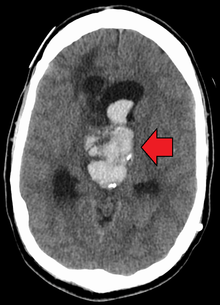

Axial CT scan of a spontaneous intracranial hemorrhage

An acute bleed into a long-standing cystic mass within the brain. Arrow points to bleeding and mass.

CT scan (computed tomography) is the definitive tool for accurate diagnosis of an intracranial hemorrhage. In difficult cases, a 3T-MRI scan can also be used.